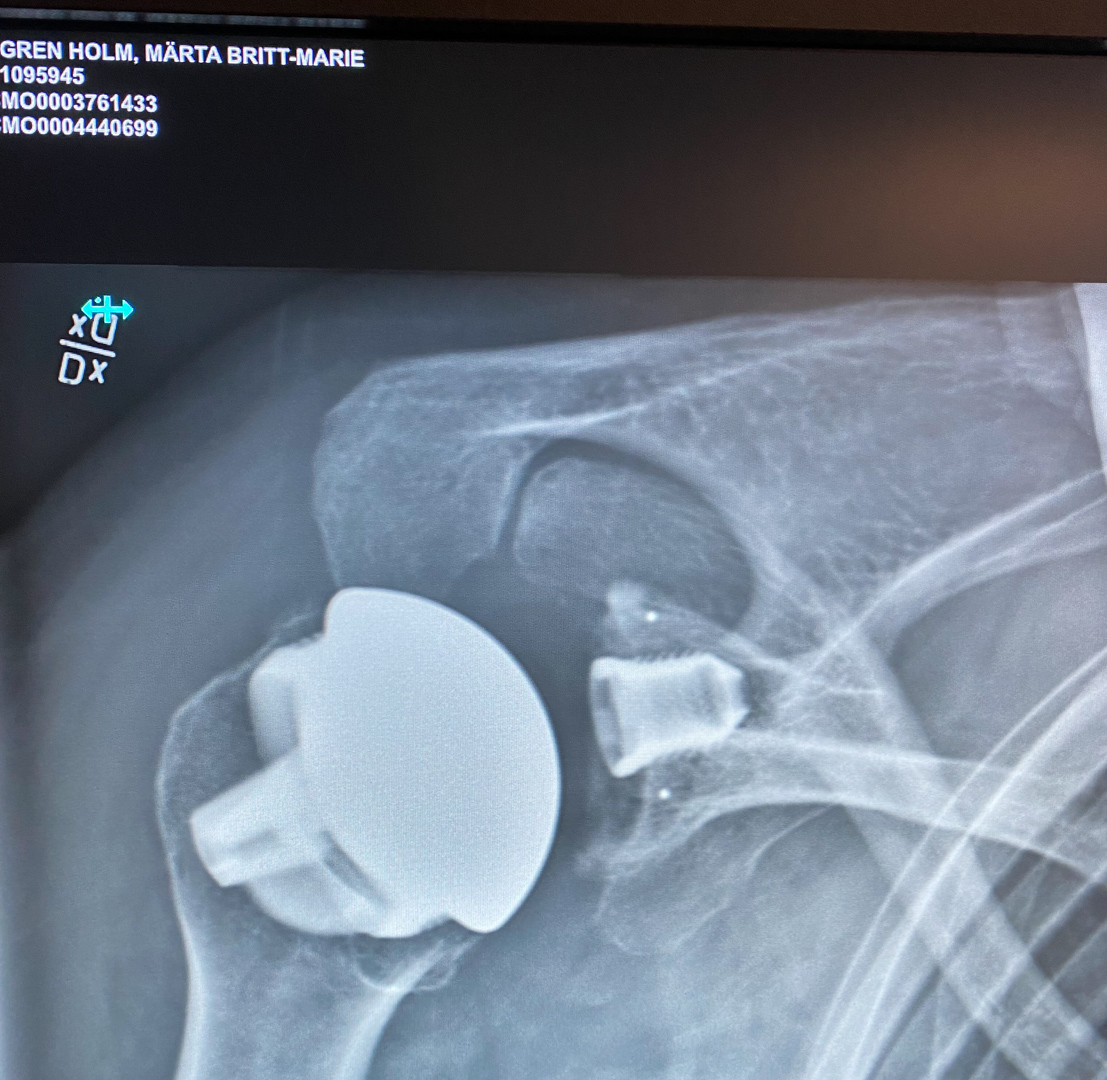

Väl där blev jag så väl omhändertagen. Vilka änglar det jobbar inom vår sjukvård och på den här avdelningen hade alla säkert gått charmkursen eller också var de bara underbara människor. Efter en sista skrubb blev jag körd mot operationsavdelningen och efter att ha fått en ordentlig nervblockad var det dags att gå in och ta plats på operationsbordet. 1,5 timme senare vaknar jag till igen och min gamla axelled där diagnosen förutom artros även var osteonekros av ledkulan (alltså att vävnaden höll på att dö), var utbytt mot en ny kula i metall och en ledyta i plast. Jag vaknar upp på avdelningen och sällan har kaffe och smörgås smakat så bra även om en var något narkosflummig.

Nästa förmiddag blev en hektisk dag med samtal med sköterska, fysioterapeut, läkare och en kontrollröntgen där vi fick med oss ett par bilder på våra nya reservdelar.

Rubriken fick jag som kommentar på ett Instagraminlägg med bl a en röntgenbild och den var för bra för att inte användas. Det färgglada hör väl till och snart övergår det antagligen i grönt och gult….Visst är det skönt att inte ha speciellt ont även om jag tänker mig noga för innan jag gör några rörelser, här ska inga ihopsydda muskler äventyras när allt har gått så bra.